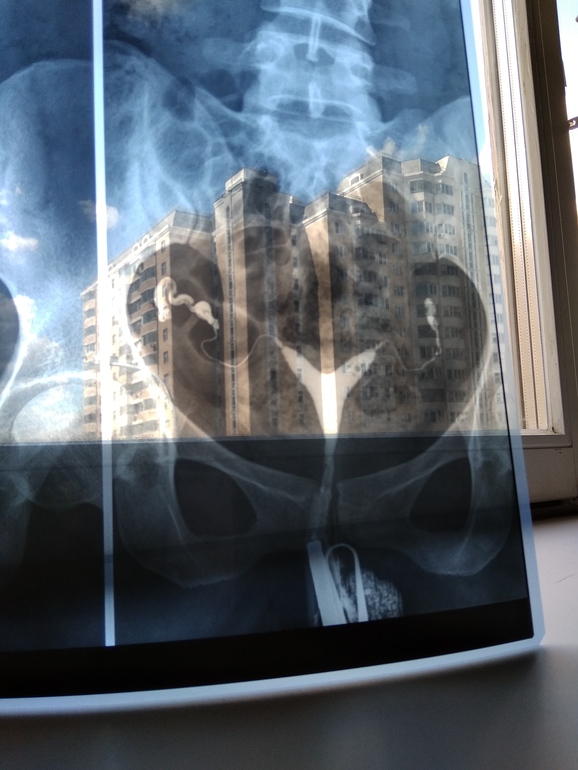

Дальше сказали идти надеть прокладку и ждать в коридоре. Когда все остальные девочки тоже прошли, врач написал заключение. Трубы проходимы! Ура))